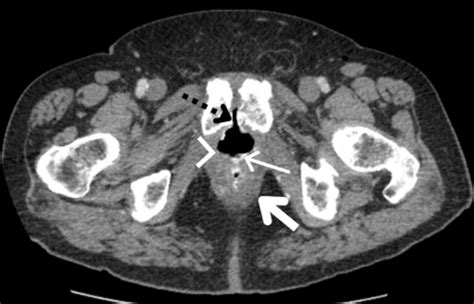

The Role of Rectal Fistula Images in Diagnosis

Accurate diagnosis is crucial for effective treatment. Rectal fistula images play a vital role in this process. These images can be obtained through various diagnostic techniques, including:

• Computed Tomography (CT) Scan: CT scans offer detailed cross-sectional images of the body, aiding in the diagnosis of complex fistulas.

These imaging techniques help healthcare providers determine the type and complexity of the fistula, which is essential for planning the appropriate treatment.